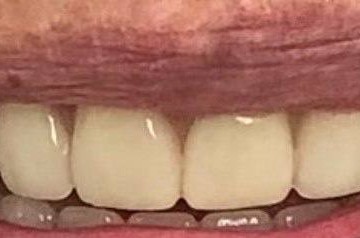

Установка коронки из диоксида циркония

Пациент, 42 года, обратился с жалобами на эстетические проблемы. Для улучшения внешнего вида его верхней челюсти были установлены коронки из диоксида циркония, которые отличаются повышенным гарантийным сроком службы. Подробнее о материале и его свойствах вы можете узнать на персональной консультации.